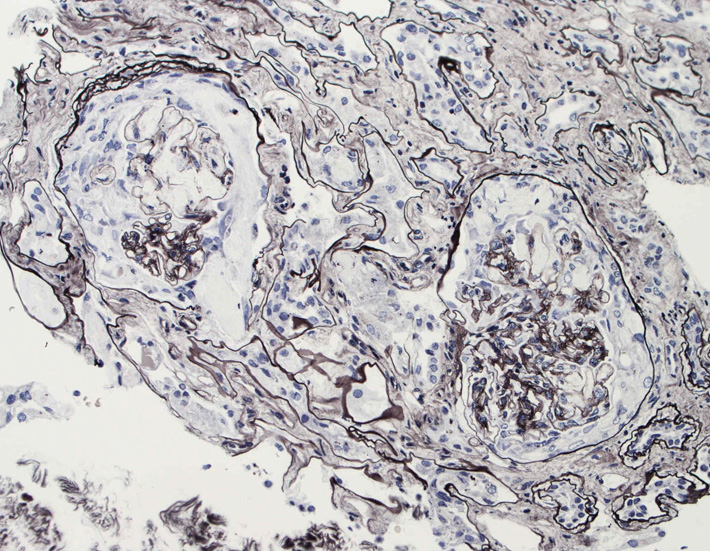

腎臓の病理組織所見-->壊死性糸球体腎炎

kidney04pas.jpg

kidney05.jpg

Fig.03(PAS)Fig.04(PAM染色)Fig.05(PAM染色)